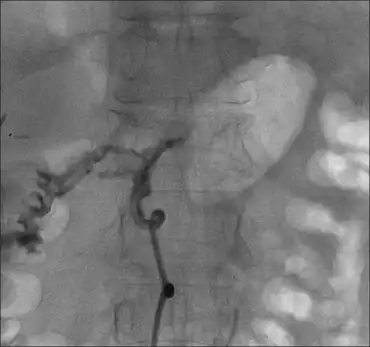

| Fistulous tracts between a pancreatic abscess and side of duodenum. | |